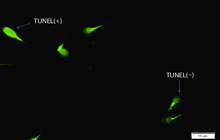

- Perform tunnel technique to evaluate apoptosis